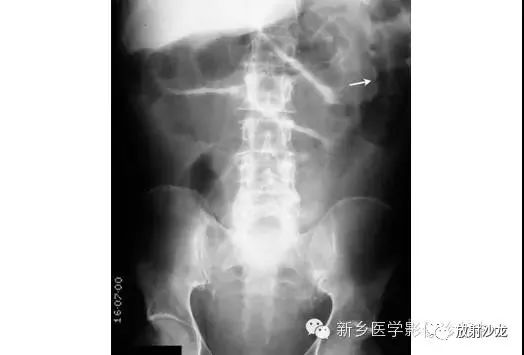

上图腹部平片检查是一6岁男孩,出现呕吐和急性右髂窝疼痛进行的。两个关键的发现在哪里?(提示:通过放射科医生所提供的箭头可以缩小关注点。)

右髂窝多个扩张的小肠襻出现小的钙化结节。小肠袢可与大肠区分开来,因为小肠的环状襞延伸至整个肠壁,而结肠袋只是部分延伸存在。在右下腹(箭头)的钙化结节高度提示阑尾粘连。这个病人开腹手术发现阑尾粘连致小肠梗阻。